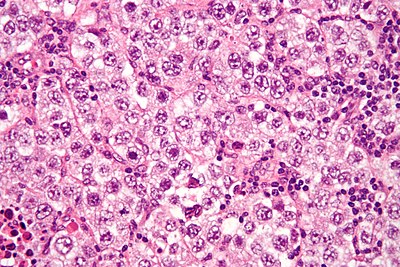

1

Diagnosis?

Seminoma high mag.jpg

Adenomatoid tumour

Adenocarcinoma of the rete testis

Adenomatous hyperplasia of the rete testis

Benign testis

Atrophic testis

Choriocarcinoma

Embryonal carcinoma

Immature teratoma

Infarcted testis

Inflamed testis

Germ cell neoplasia in situ

Leydig cell tumour

Lymphoma

Mature teratoma

Mixed germ cell tumour

Papillary cystadenoma of the epididymis

Seminoma

Spermatocytic tumour

Sertoli cell tumour

Sertoli cell nodule

Testicular scar

Yolk sac tumour